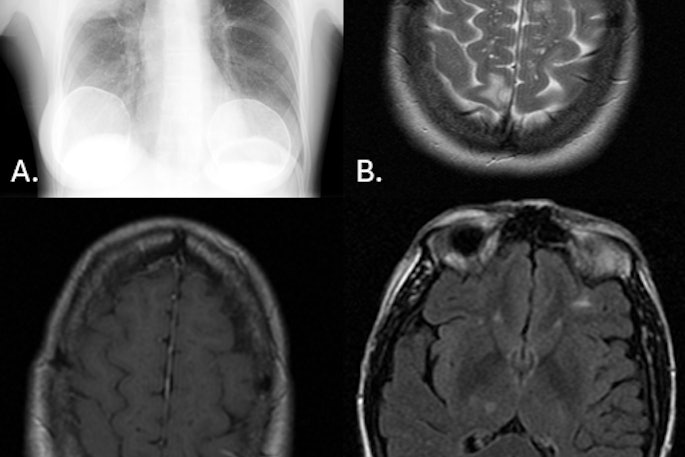

Cases of the Week

Check out our Cases of the Week!